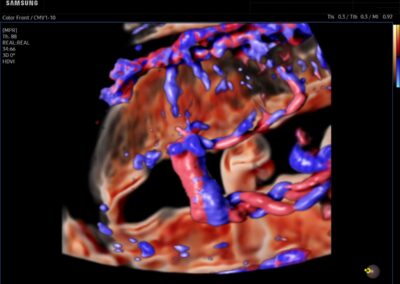

Procedural Services

Comprehensive, advanced and expert MFM care for high-risk pregnancies

- Fetal anomalies